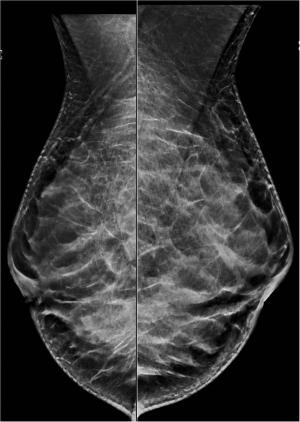

Image IQ: Screening Ultrasound for Dense BreastsByStamatia Destounis, MDNovember 4th 201647-year-old patient offered screening ultrasound due to dense breast tissue.